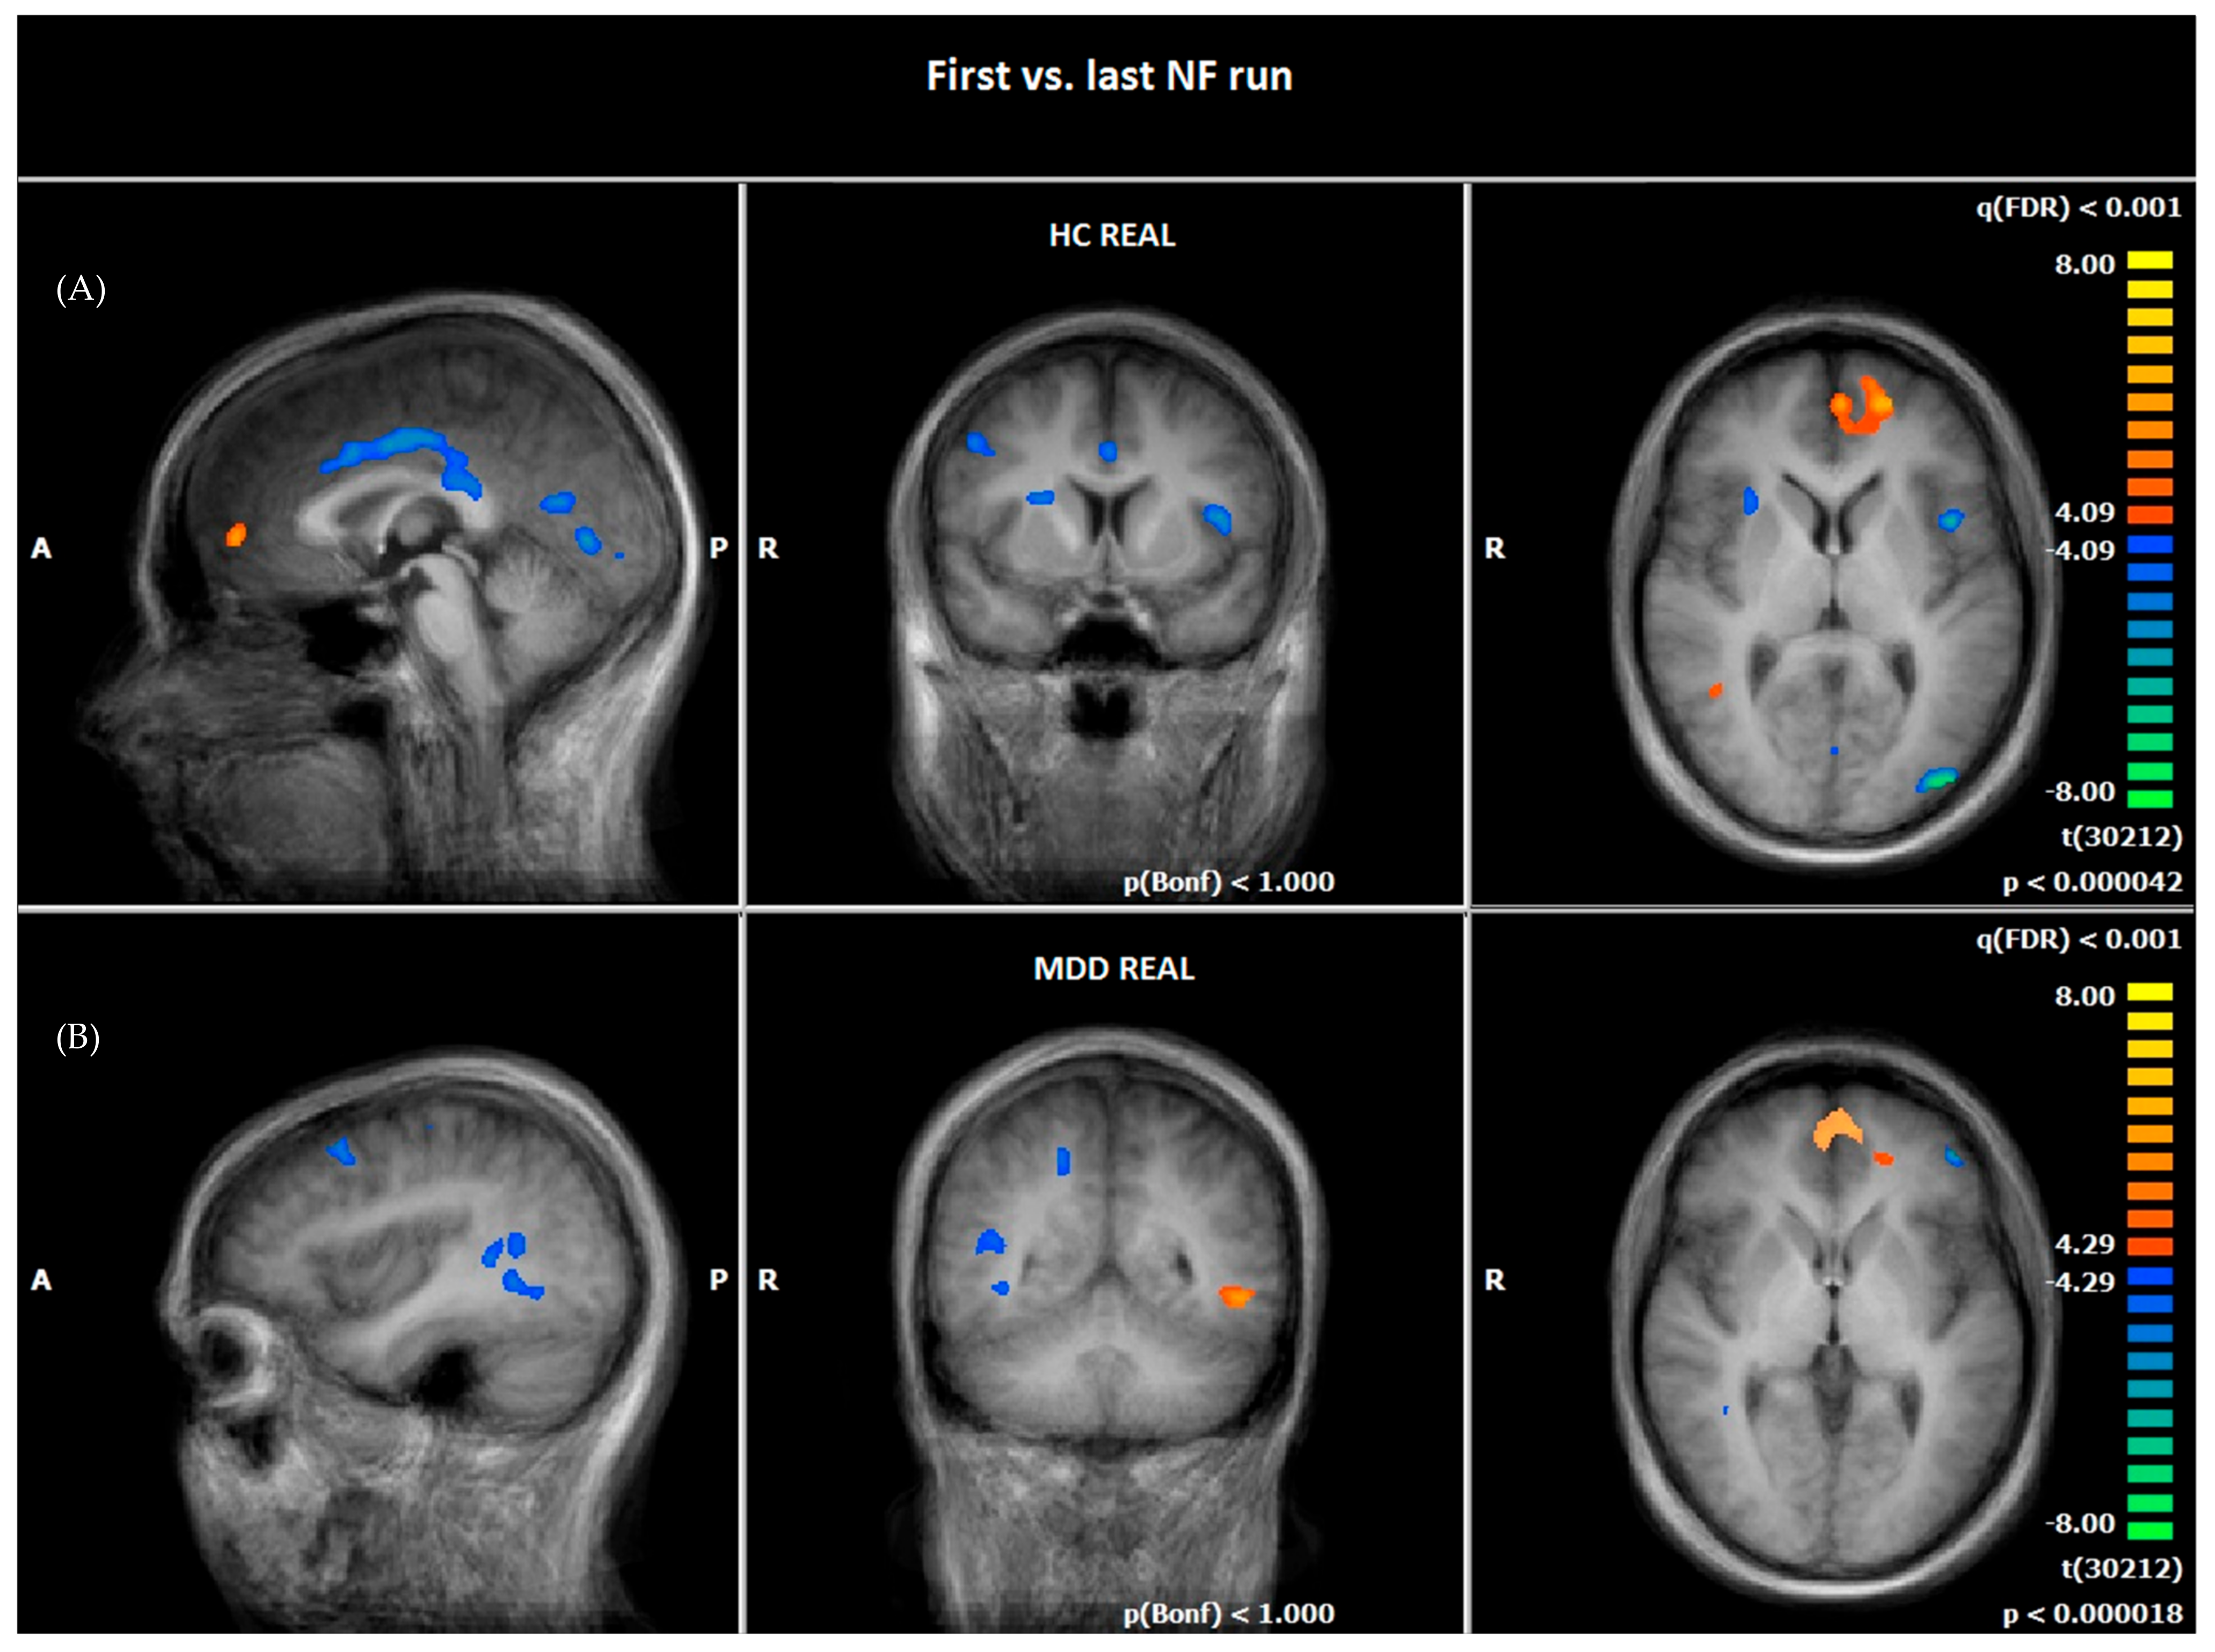

3.4. Comparison of Hemodynamic Responses between the First NF Run on Day One and the Last NF Run on Day Two: MDD REAL and HC REAL

4.2.2. Comparison of Hemodynamic Responses between the First and the Last NF Run